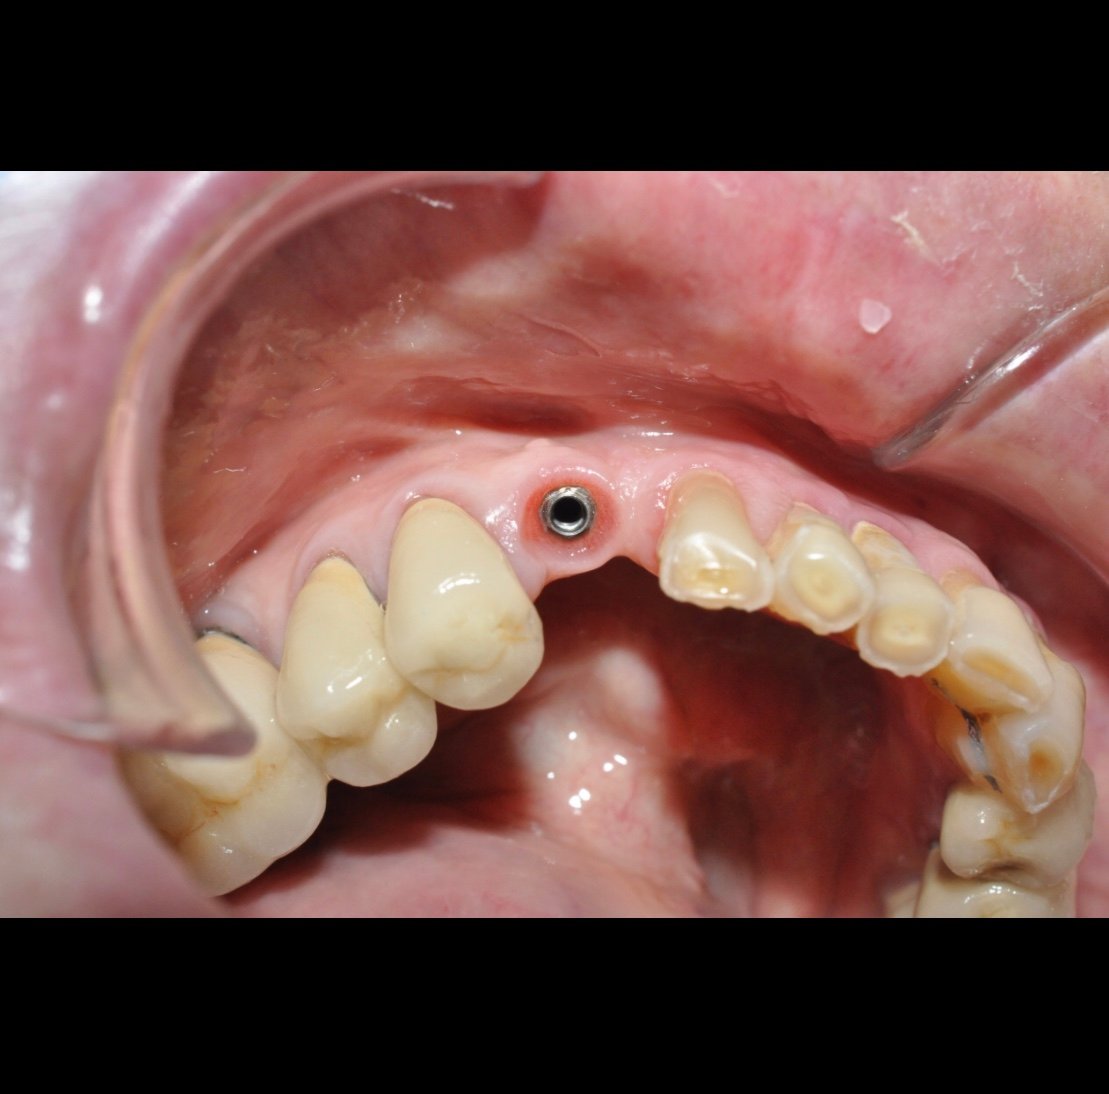

Hola, a las este paciente se le afloja la corona y no conseguimos dar con el destornillador apretarlo. Hemos intentado con un destornillador klockner pero no hemos podido. Os adjunto [...]